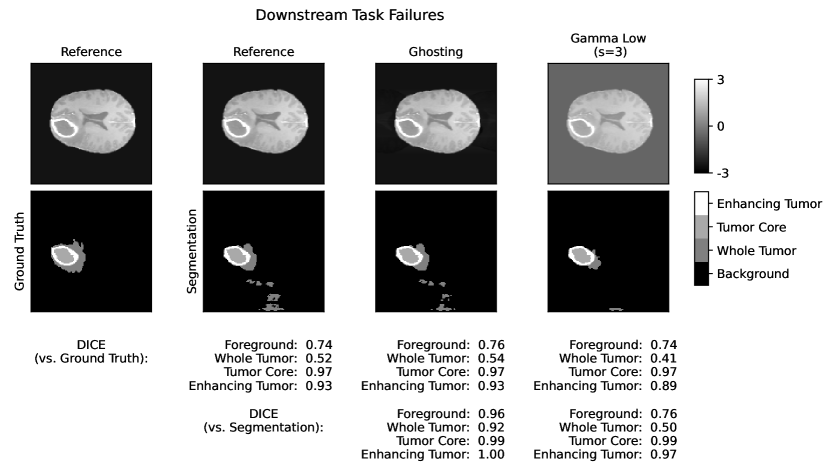

The segmentation scores (see Tab. 5, and Fig. A.4) for all three classes are very similar. Intensity shift has no effect due to preprocessing with z-score normalization. The effect of elastic deforms and ghosting artifacts on the segmentation are very limited. Gaussian noise and stripe artifacts most strongly impair segmentation. Translated segmentations have decreasing overlap and thereby very low DICE scores.

5 Adverse Examples

In the following, special characteristics of the analyzed metrics, which can be derived from their definition or the experimental results above, are show-cased. We present adverse examples (see Fig. 2-6), where similarity metrics do not perform as intended or expected.

Replace artifacts remain underestimated by most similarity metrics. For those artifacts, that resemble structures of diagnostic interest, the evaluation of segmentations with a specific segmentation model is useful. In our evaluation, we use a segmentation model, that was trained to detect different tumor regions. It successfully detects replace artifacts, where the tumor is doubled or removed.